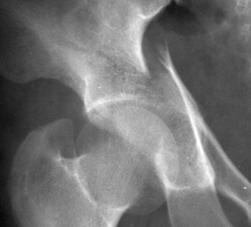

Fractura de acetabul Fractura de acetabul. Aspect CT